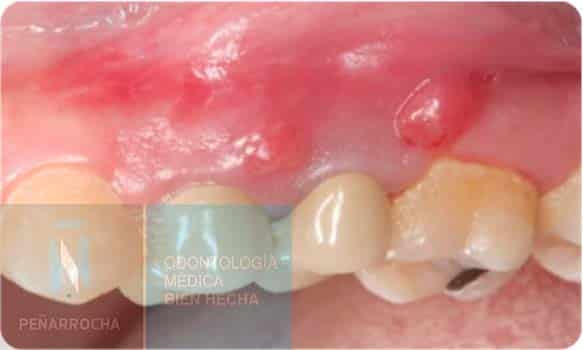

Swelling of the Gum or Affected Area

Inflammation around the treated tooth can appear as localized swelling in the gums and, in some cases, as visible swelling in the face. The extent of the infection and the location of the tooth determine how severe the swelling may become.

If left untreated, the infection may progress into an acute periapical abscess, with pus formation, increased pain, and even general malaise. In such cases, immediate consultation with an endodontist is essential.

Fistulas or Pus Discharge

Fistulas appear as small whitish bumps near the affected tooth. They act as drainage points for pus caused by infection. Although they may not always be painful, fistulas are a sign of an active infection inside the tooth.

These lesions may come and go intermittently. Without proper treatment, the infection can spread to the surrounding bone or soft tissues. A clinical exam combined with X-rays or CBCT imaging is needed for a definitive diagnosis.